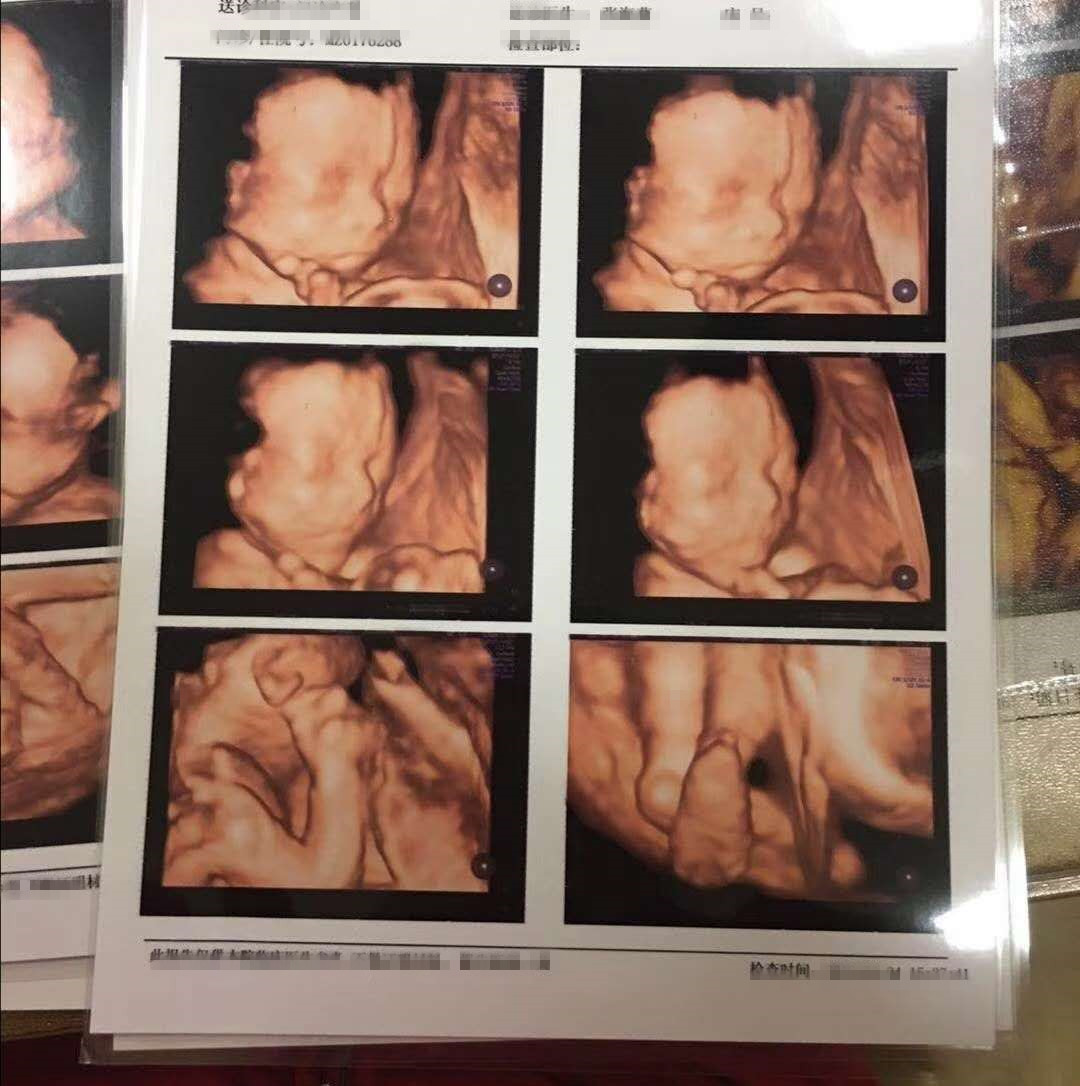

还有几个月我们就要和两个小天使见面了,上个月照过了思维彩超,透着小小的显示屏看到两个小宝宝皱皱巴巴地蜷缩在一块儿,感慨生命真的很奇妙。在这一片岁月静好的背后,确实一段七年不孕的辛酸往事。

如今,已经安全度过四维了,七年的不放弃终于换来了一个圆满的结果,我们已经给即将诞生的两个小天使准备好了一切行头,让他们知道爸爸妈妈有多么殷切地期待他们的到来。希望大家都能圆梦,等待有所值!